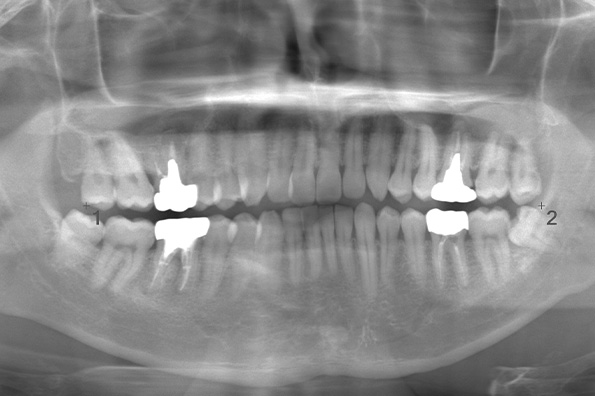

CASE 11

| 年齢・性別 | 33歳・男性 |

| 主訴 | 左上下親知らず抜きたい |

| 抜歯期間 | 30分 |

| 抜歯費用 | 約2,500円(保険内) 別途CT撮影で3,000円 (2022年7月現在) |

| 抜歯内容 | 左上下の親知らず抜歯 |

| 治療方針 |

初めに右下の奥歯が痛いとのことでご来院されました。 右下の親知らずと7番目の歯がカリエスになっていたため、まずは右下の親知らず抜歯と7番目の感染根管治療を行いました。左上下の親知らずもカリエスになっているため、今回抜歯を行いました。 |